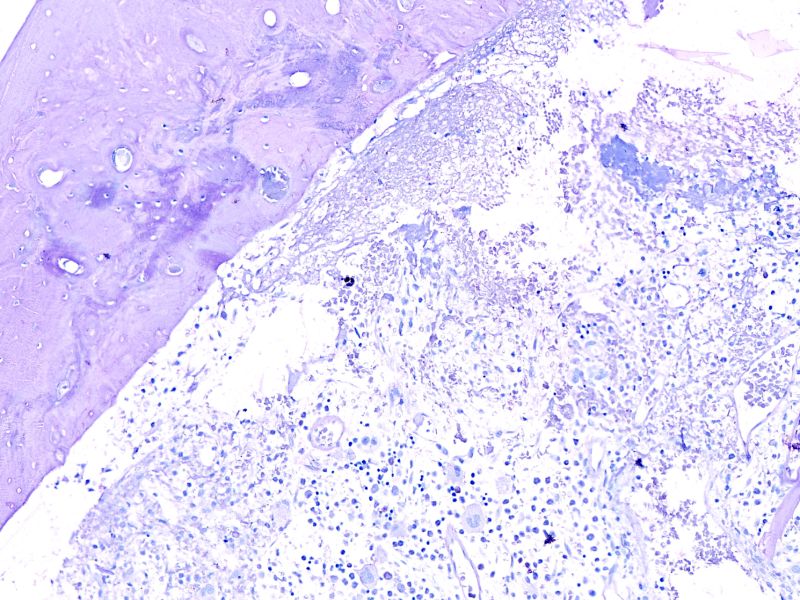

HE染色

普鲁士蓝染色

编号:YSY10122